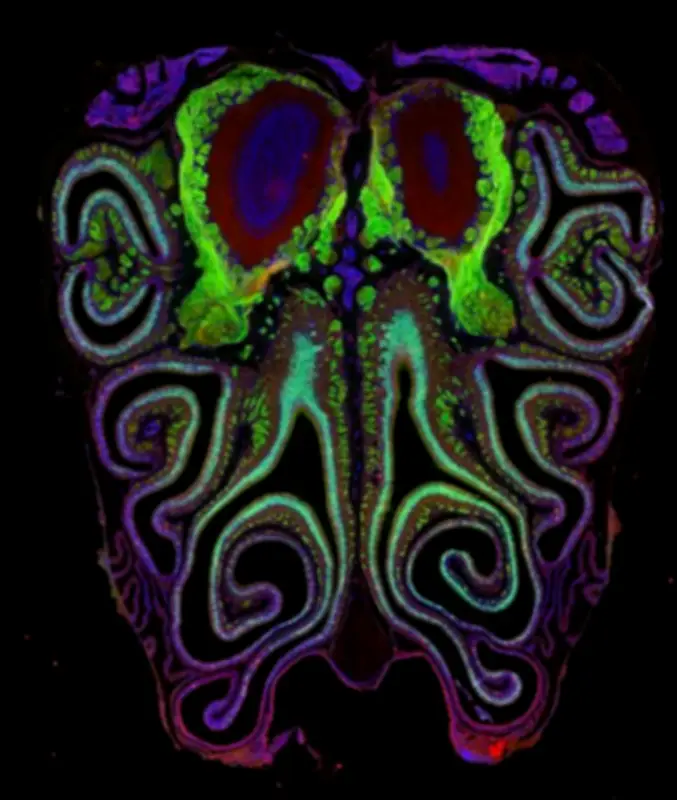

Según el estudio, el tejido olfativo funciona como un sistema que regula de manera coordinada la expresión de cientos de genes. En particular, alrededor de 250 genes siguen gradientes de actividad a lo largo del eje dorsal a ventral (de arriba hacia abajo en la cavidad nasal). Esto crea una especie de “mapa molecular” en el que cada zona tiene una identidad genética propia, guiada por señales como el ácido retinoico, que varía según la posición.

En palabras más sencillas, parece que la nariz funciona como un territorio organizado. Cada zona tiene “reglas” propias que influyen en lo que pueden hacer las células que se ubican allí. Esas reglas vienen dadas por la actividad de ciertos genes, que no se activan igual en todas partes, sino que cambian gradualmente de arriba hacia abajo dentro de la cavidad nasal. Esto crea una especie de mapa. Dependiendo de dónde esté ubicada una célula, recibe distintas señales químicas, como el ácido retinoico, que le indican qué tipo de receptor expresar. Cada célula no elige libremente, sino que tiene un conjunto de opciones definido por su ubicación.